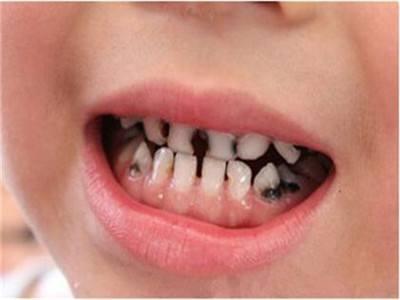

宝宝6-12岁在换牙时,因乳牙滞留、错颌、多生牙引起的牙齿不齐的情况特别常见。这个时期如果存在乳牙不正或龋齿的现象一定要及时治疗,改善宝宝面形和牙齿功能。